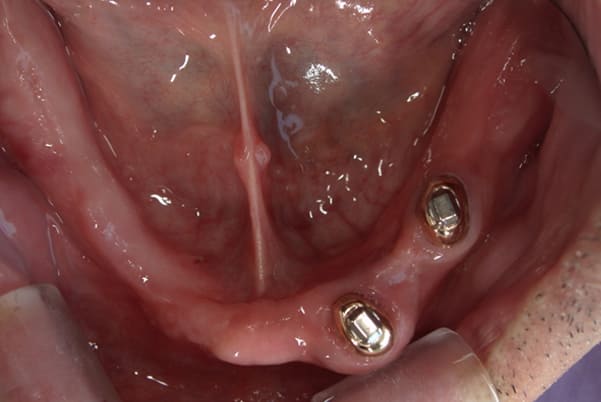

上顎治療前

-

上顎治療後

根のみの7本は虫歯にもなっており歯肉は腫れあがっています。

残りの歯もレントゲンで重度の歯周炎によりぐらぐらな状態でした。